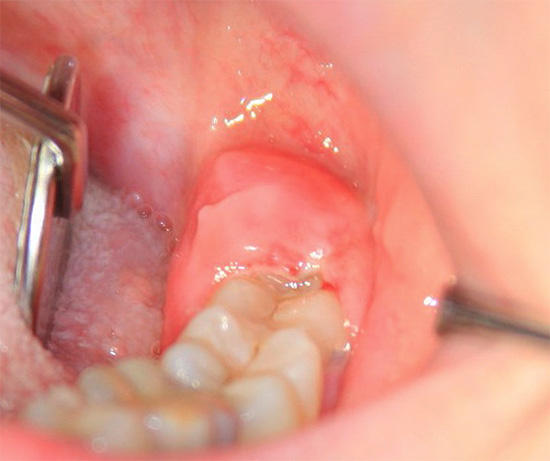

A foto mostra como fica o buraco após a extração do dente após 3 semanas:

Se o processo não é complicado por alveolite, geralmente cerca de 7 dias após a extração do dente, o tecido de granulação substitui quase completamente o coágulo sanguíneo e um osso jovem é formado ativamente. Quanto tempo o orifício crescerá após a extração do dente, para que uma gengiva lisa se forme completamente, depende da natureza da intervenção. Quanto mais grossa a remoção e mais danificados os tecidos circundantes, mais tempo a ferida cicatrizará.

Segundo as estatísticas, a cura normal deve terminar em 2-3 semanas, mas isso não significa que nada aconteça no buraco. A formação completa do tecido ósseo sob a gengiva geralmente termina apenas após 2-3 meses e, a partir do orifício anterior, no qual o paciente estava anteriormente, não há mais vestígios.